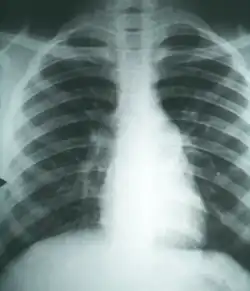

Imaging

Chest X-rays rarely demonstrate lung nodules or cavities. These images commonly demonstrate lung opacification, pleural effusions, or enlargement of lymph nodes associated with the lungs.[4] Computed tomography scans of the chest are more sensitive than chest X-rays to detect these changes.[4]